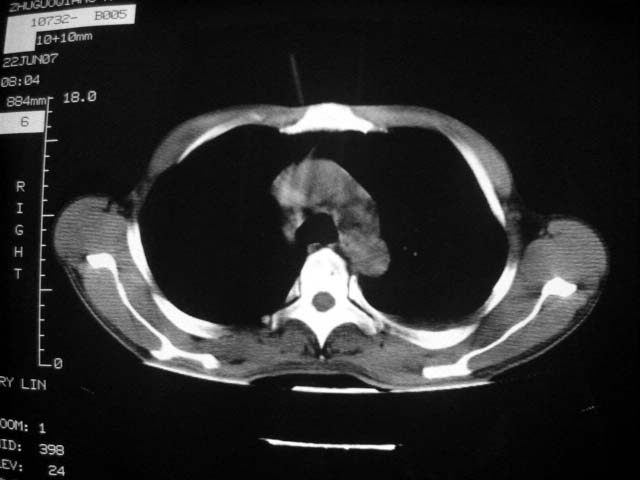

近2个月病灶变化较大,应是感染性病变,首先考虑金黄色葡萄球菌感染。

回顾既往片,病变明显吸收,缩小,未经治疗,不支持肺转移瘤,可能为肺结节病或韦格氏肉芽肿

支持韦格氏肉芽肿